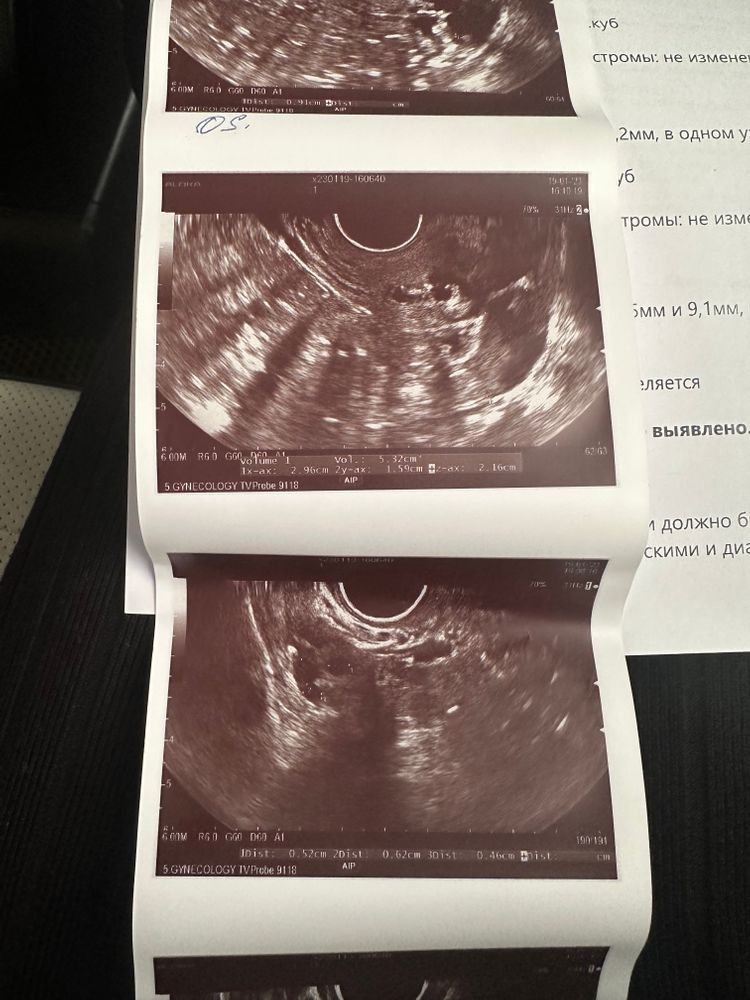

Виктория Виктория в Зачатие 3 года Девочки, оказывается овуляции не произошло…ДФ был, а сегодня его уже нет и желтого тела тоже нет…((( Ждем дня Х (Признаки беременности / Тесты) Посмотрите еще 20 записей на эту тему Отменить Ответить Вероника Так может у вас позже будет ещё овуляция в этом цикле,там вон фолликул 10мм почти… 19.01.2023 Ответить Зима А хгч почему вырос не сказали ? 19.01.2023 Ответить Жду результат 8 дпо Ближе к вечеру тянет немного живот,грудь не болит но тяжелая Чаты Беременных Выберите чат: Январята-2026 Февралята-2026 Мартята-2026 Апрелята-2026 Майчата-2026 Июнята-2026 Июлята-2026 Августята-2026